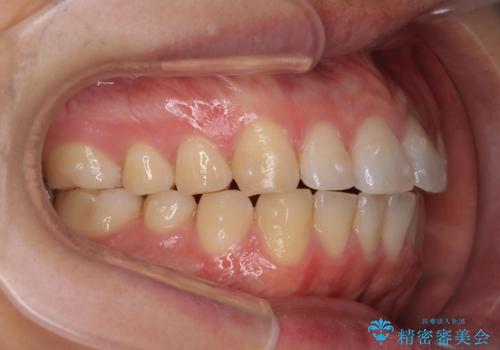

前歯が気になる。インビザラインライト

- 前歯が気になるとの事で来院。

矯正を希望されたが費用と時間を抑えたいとの事でインビザラインライトで矯正を行いました。(奥歯の位置関係はほぼ変えない)

前歯が綺麗に並び大変満足して頂けました。